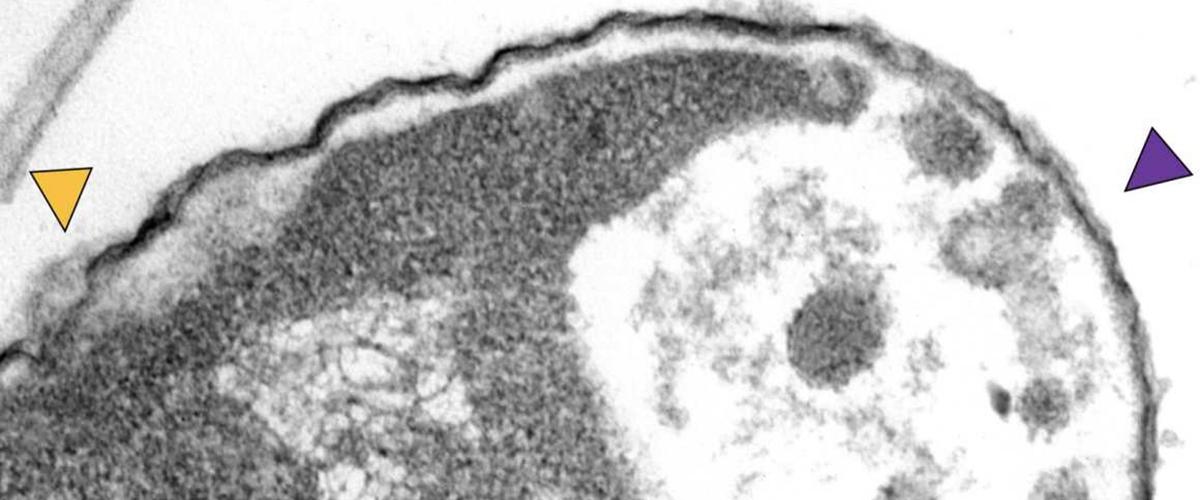

Ученые разработали специальные молекулы, которые ищут клетки-мишени и прикрепляются к их поверхности. После активации светом они начинают вращаться со скоростью до 3 млн оборотов в секунду, проделывая отверстие в клеточной стенке. Это либо убивает бактерию само по себе, либо открывает путь внутрь клетки антибиотикам — в том числе тем, против которых у нее уже выработалась устойчивость.

Эксперименты на бактерии Klebsiella pneumoniae подтвердили эффективность новой методики. Использование «молекулярной дрели» убило 17% бактерий, а в сочетании с антибиотиком меропенемом — 65%. Небольшая модификация увеличила эту цифру до 94%.